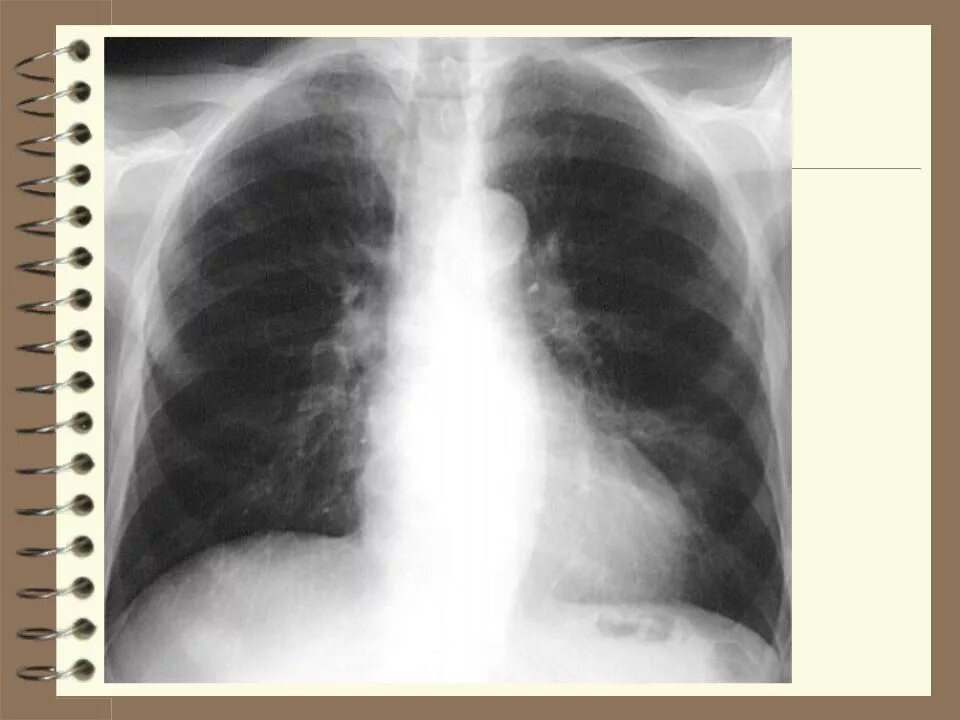

Что значит аорта уплотнена на флюорографии